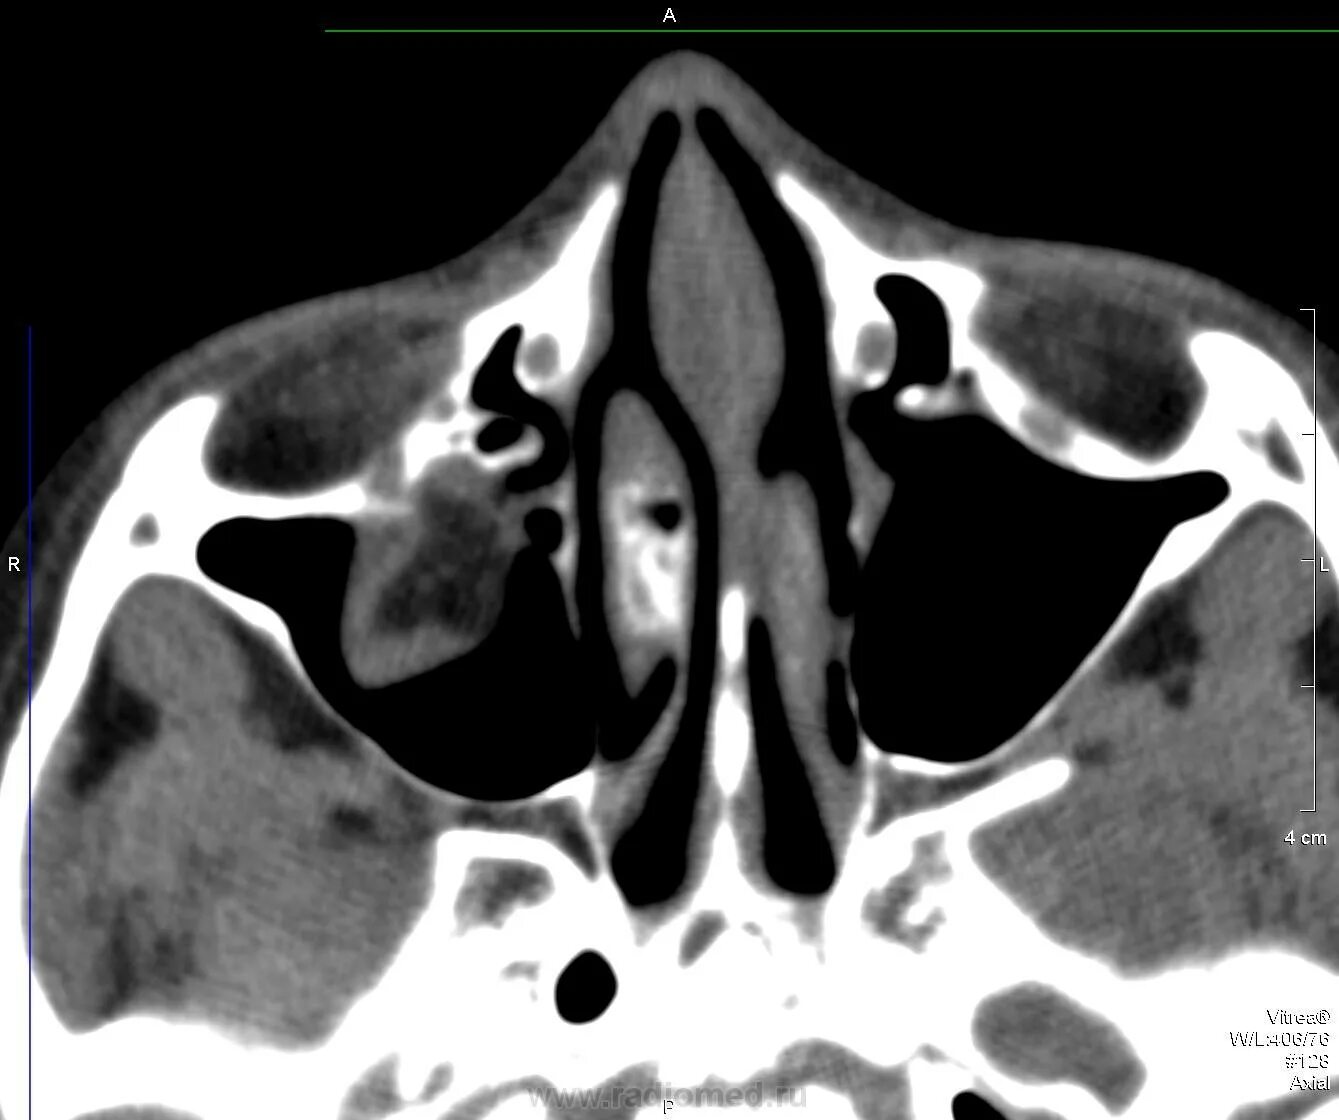

Перелом стенки левой орбиты